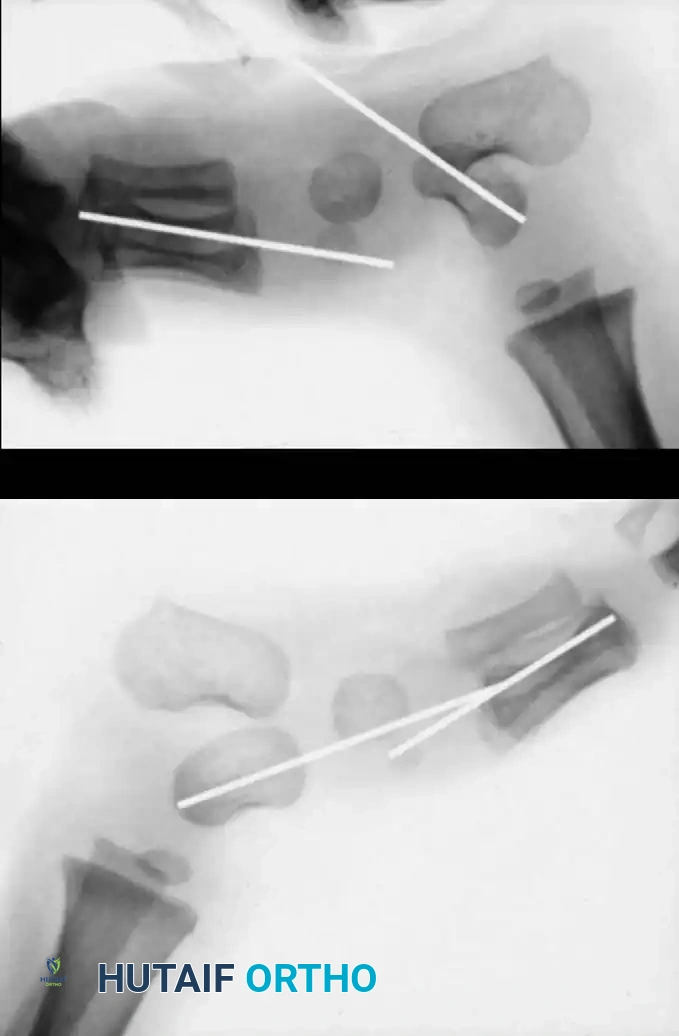

Differentiating CVT from severe but flexible pes planus or oblique talus requires rigorous radiographic evaluation. Standard weight-bearing (or simulated weight-bearing in infants) anteroposterior (AP) and lateral radiographs are required. However, the definitive diagnostic view is the plantar flexion lateral stress radiograph.

- Normal Foot / Flexible Pes Planus: On a plantar flexion lateral view, the long axis of the first metatarsal aligns with or passes plantarward to the long axis of the talus, indicating that the talonavicular joint is reducible.

- Congenital Vertical Talus: On the plantar flexion lateral view, the long axis of the first metatarsal remains rigidly dorsal to the long axis of the talus. This confirms the irreducible dorsal dislocation of the midfoot and forefoot on the hindfoot.

Surgical Warning: Failure to obtain a forced plantar flexion lateral radiograph can lead to misdiagnosis of an oblique talus as a true vertical talus, potentially resulting in unnecessary or overly aggressive surgical intervention.